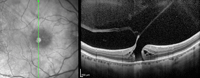

Figura 30. Agujero macular miópico, con tracción y esquisis macular.

Figura 31. Agujero macular miópico, con tracción y esquisis macular, al mes de realizar cirugía de vitrectomía.

Figura 32. Agujero macular miópico, con tracción y esquisis macular, a los 6 meses de realizar cirugía de vitrectomía.

Figura 33. Esquisis con tracción en paciente miope con estafiloma posterior.